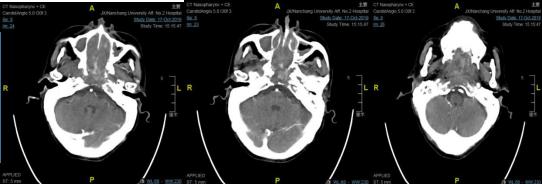

该患者是一位70岁男性,21年前患者因"鼻咽恶性肿瘤"曾行放疗,于5月余前出现鼻腔反复出血,伴鼻塞、说话含糊不清,反复至国内多家三甲医院就诊,因患者年事已高、体质差,均未能给予进一步治疗。因反复出血,致使老人每日生活在恐惧之中,期盼着能得到救治。进入南大二附院耳鼻咽喉头颈外科治疗时,患者已合并极重度贫血、低钠低氯血症、低蛋白血症,并且仍有反复出血、纳差,入院诊断:鼻咽恶性肿瘤,失血性贫血,低钠低氯血症,低蛋白血症。该科鼻-鼻颅底团队经过反复讨论,针对患者病情危重、肿瘤巨大、体质差易导致手术风险和难度极大的情况,鼻-鼻颅底团队认真制定手术方案,决定先行介入下颈外动脉栓塞,再在全麻下行鼻内镜下鼻咽颅底肿瘤扩大切除术。

10月21日,南大二附院综合介入室陈平主任带领的介入团队于局麻下行血管介入下颈外动脉栓塞,完成介入手术后立即送至手术室,由盛洪广主任带领的麻醉团队成功完成全身麻醉,由耳鼻咽喉头颈外科鼻-鼻颅底团队在全身麻醉下行鼻内镜下鼻咽颅底肿瘤扩大切除术,术中顺利切除鼻咽部巨大肿瘤,并将侵犯蝶窦、斜坡、左侧破裂孔区肿瘤完整切除,术中出血不多,手术全程仅用时2小时。

手术前

手术后